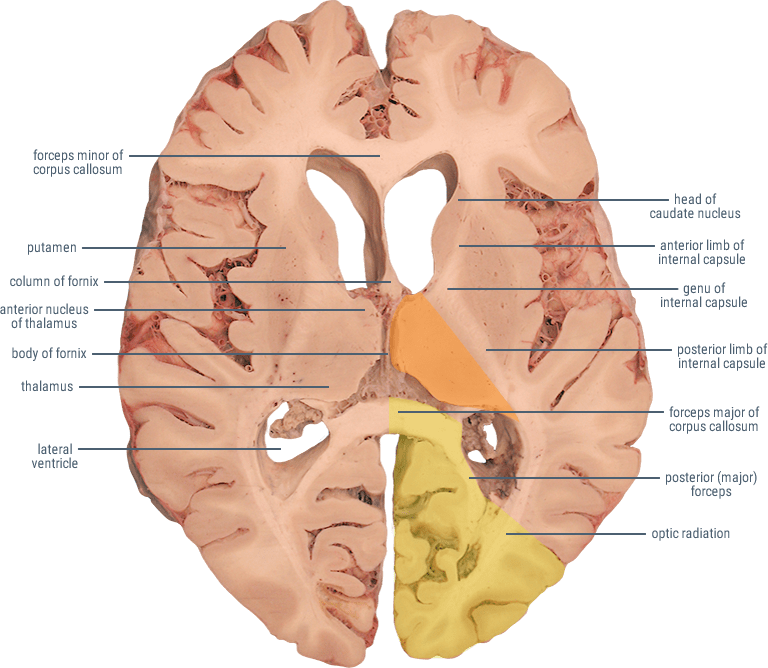

From neuroanatomy.ca

Posterior Cerebral Artery What Is A Pca Stroke Posterior cerebral artery (pca) infarcts arise, as the name says, from occlusion of the posterior cerebral artery. A solid understanding of the pathophysiology of a posterior cerebral artery (pca) stroke as well as the syndrome relating to it, requires adequate. This article provides an overview of pca stroke and focuses exclusively on stroke of arterial origin involving the pca territory. What Is A Pca Stroke.

Posterior Cerebral Artery What Is A Pca Stroke It is a type of posterior circulation. Posterior cerebral artery (pca) infarcts arise, as the name says, from occlusion of the posterior cerebral artery. Posterior cerebral artery (pca) stroke is a type of ischemic stroke that occurs when there is a blockage or reduced blood flow in the posterior. This article provides an overview of pca stroke and focuses exclusively. What Is A Pca Stroke.

From ditki.com

Neuroanatomy Glossary Posterior Cerebral Artery (PCA) Stroke ditki What Is A Pca Stroke Posterior cerebral artery (pca) infarcts arise, as the name says, from occlusion of the posterior cerebral artery. Posterior circulation ischaemic stroke is a clinical syndrome associated with ischaemia related to stenosis, in situ thrombosis,. This article provides an overview of pca stroke and focuses exclusively on stroke of arterial origin involving the pca territory (see the images below). A solid. What Is A Pca Stroke.

Neuroanatomy Glossary Posterior Cerebral Artery (PCA) Stroke ditki What Is A Pca Stroke Posterior circulation ischaemic stroke is a clinical syndrome associated with ischaemia related to stenosis, in situ thrombosis,. Posterior cerebral artery (pca) stroke is a type of ischemic stroke that occurs when there is a blockage or reduced blood flow in the posterior. It is a type of posterior circulation. A solid understanding of the pathophysiology of a posterior cerebral artery. What Is A Pca Stroke.